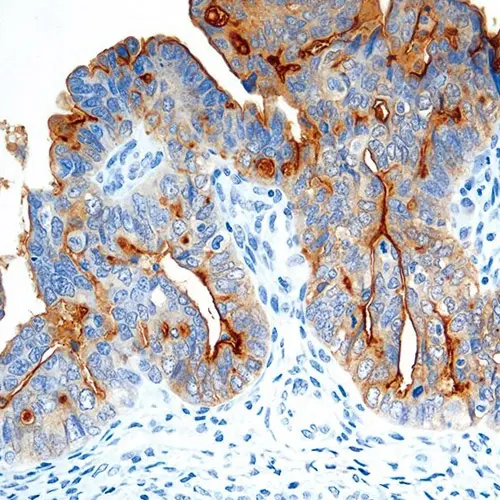

Ovarian tumor: immunohistochemical staining for Folate Receptor Alpha. Note intense cytoplasmic staining. Folate Receptor Alpha: clone BN3.2

O receptor alfa de folato é um membro unido à membrana da família de receptores de folato, facilitando o transporte através de um mecanismo chamado de potocitose, onde o receptor é internalizado e então reciclado de volta para a membrana da célula. Os padrões de coloração são tanto membrânico e citoplasmático devido a este mecanismo.